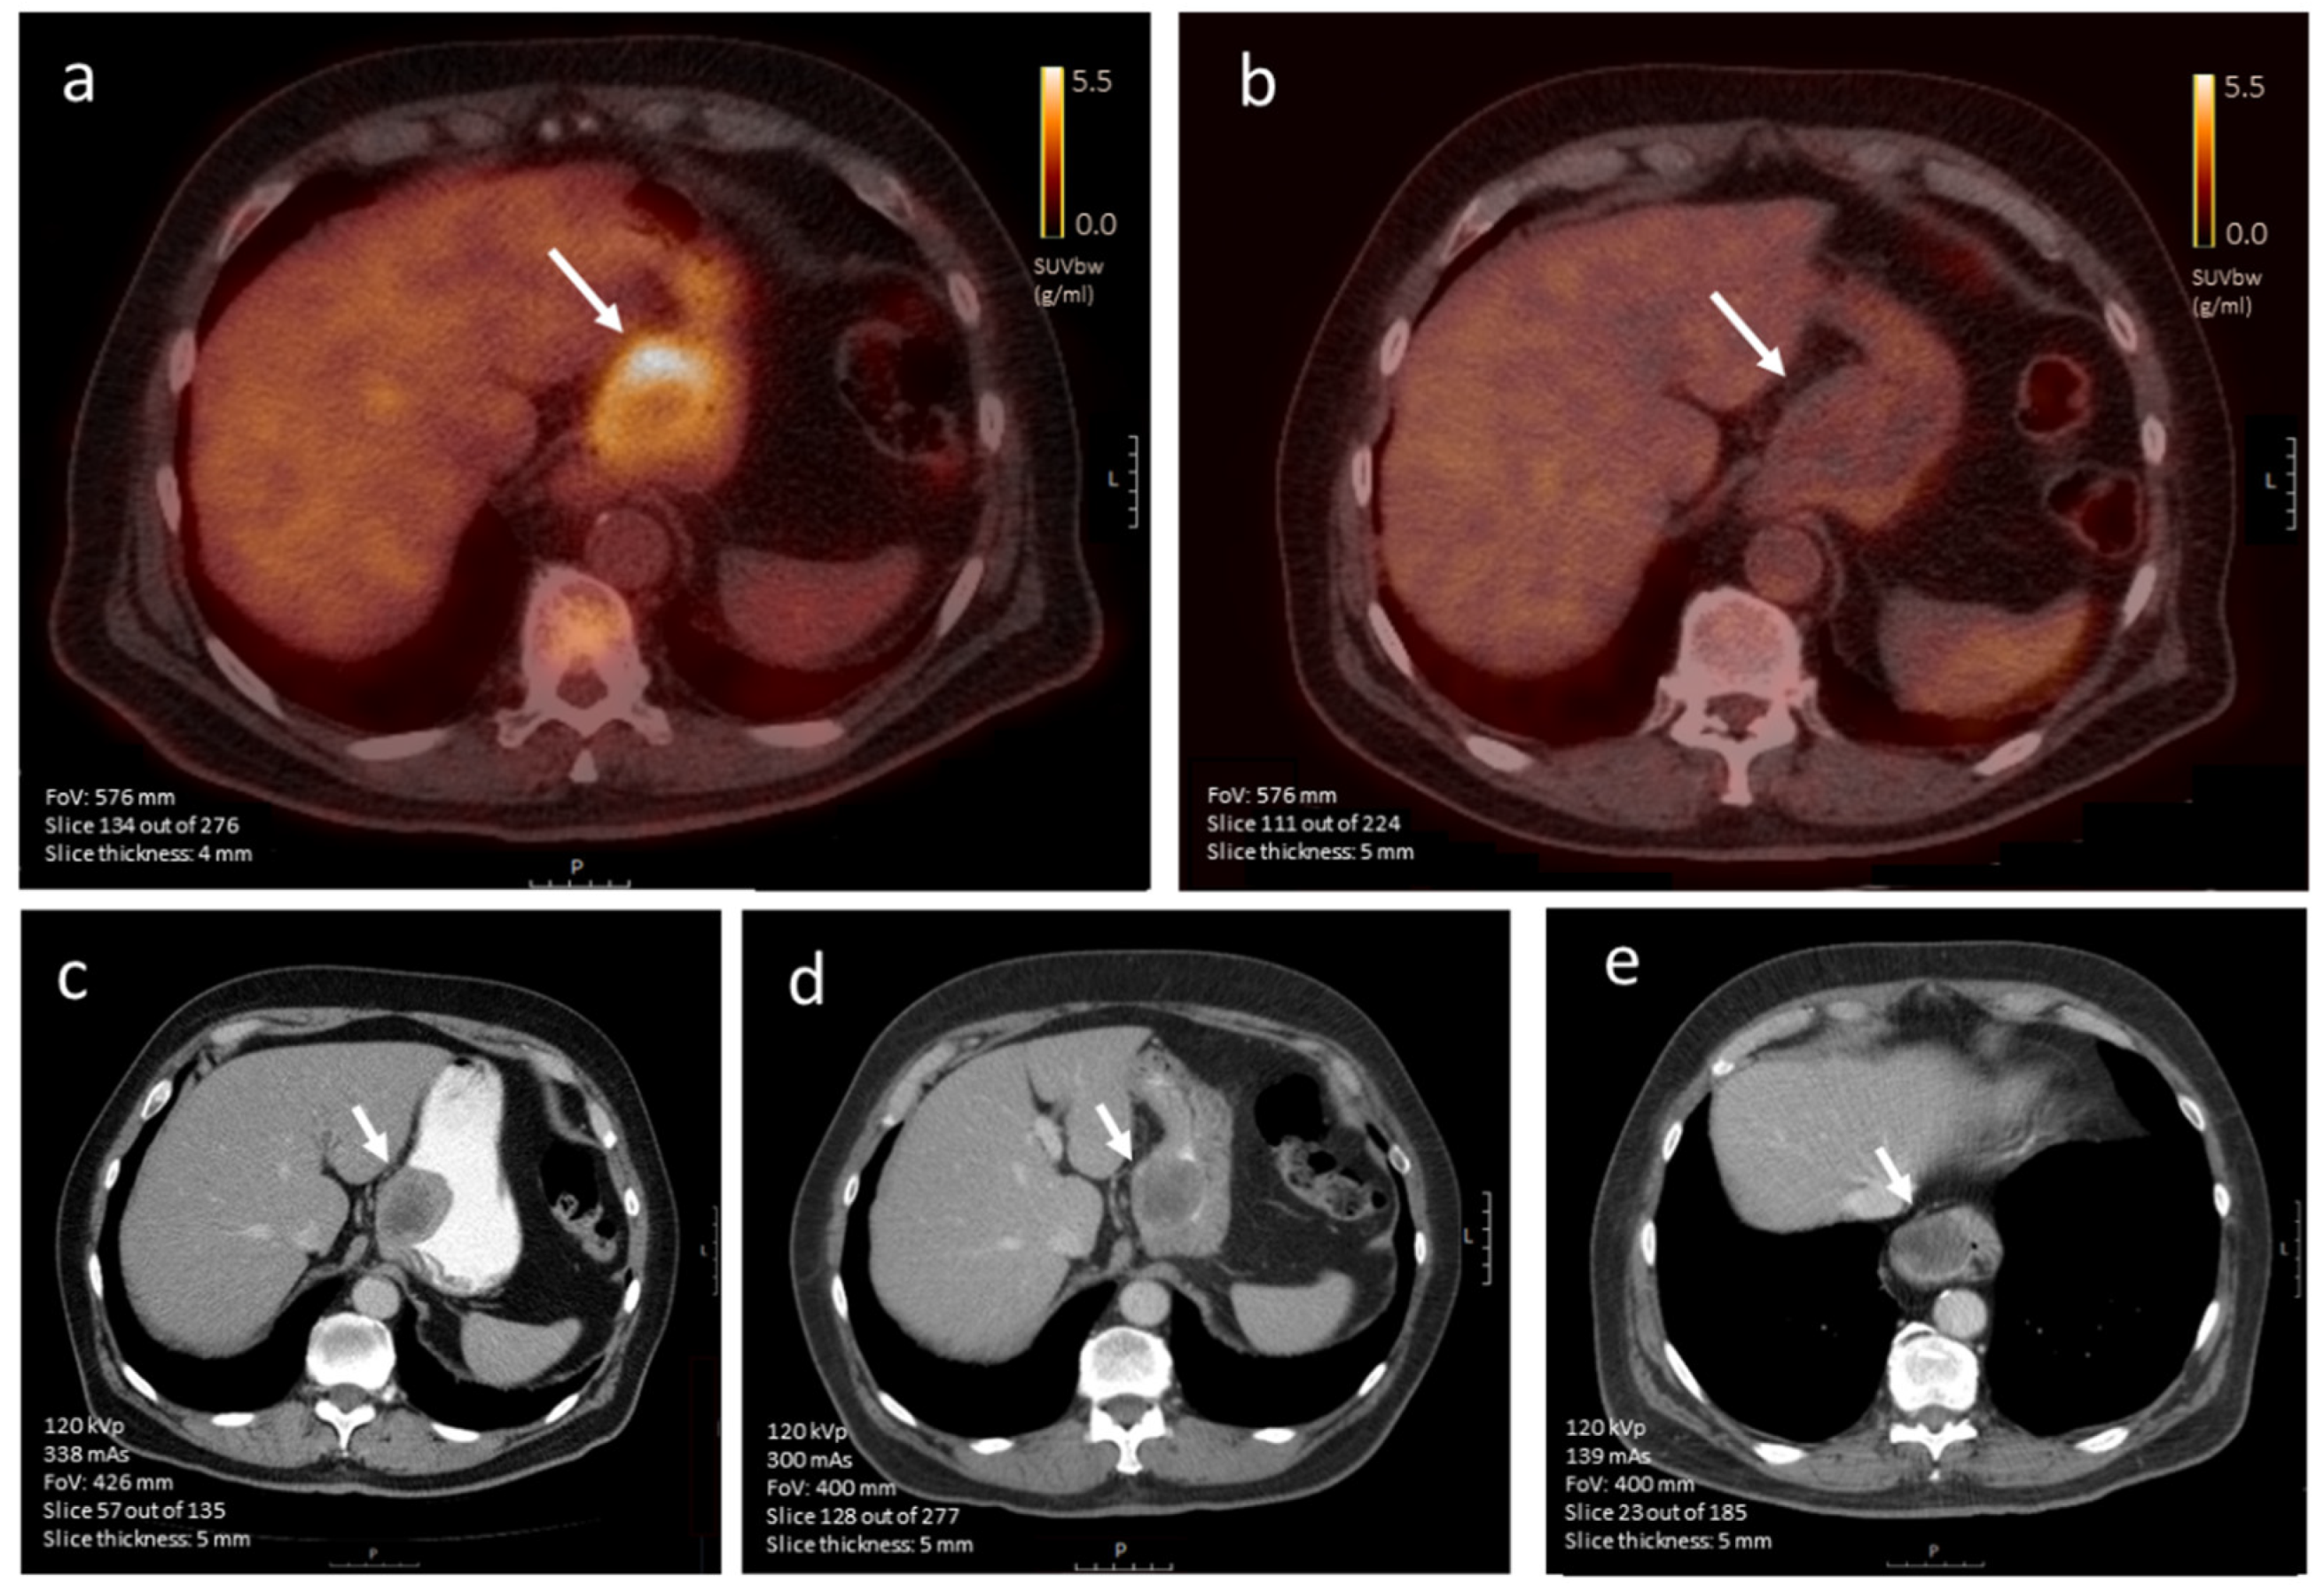

3.4.3. CE-CT vs. [18F]FDG-PET Imaging